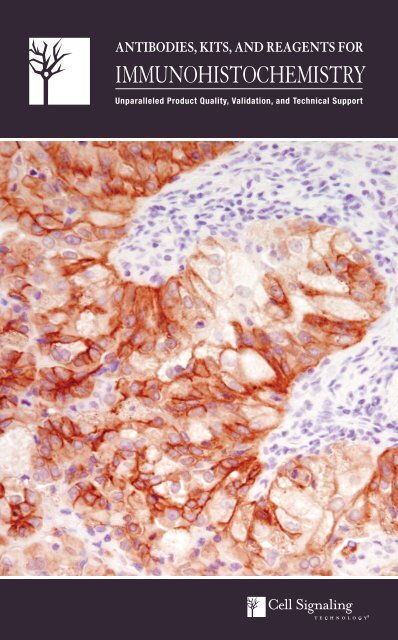

ANTIBODIES, KITS, AND REAGENTS FORIMMUNOHISTOCHEMISTRYUnparalleled Product Quality, Validation, and Technical Support

Antibody Validation for ImmunohistochemistryCell Signaling Technology (CST) antibodies have been extensively validated by ourin-house immunohistochemistry (<strong>IHC</strong>) group in tissue samples and clinically relevantmouse models. Target specificity for <strong>IHC</strong> analysis is determined throughmultiple validation steps. Our in-house <strong>IHC</strong> group uses a variety of approaches foreach antibody validated for use in <strong>IHC</strong> to demonstrate that staining achieved withthe antibody is specific and accurate.#4060UntreatedLY294002Western Blot Analysis: CST antibodies are initially tested by western blot, andonly antibodies that yield clear bands of the appropriate molecular weight with nosignificant additional cross-reacting bands are chosen for validation in applicationssuch as <strong>IHC</strong>.Paraffin-embedded Cell Pellets: Cells are subjected to treatments known toinduce signaling changes to verify modification specificity (e.g. phosphorylation,acetylation, cleavage, etc.). To determine phospho-specificity of Phospho-Akt(Ser473) (D9E) XP ® Rabbit mAb #4060, LNCaP cells were treated with the PI3Kinhibitor LY294002 #9901, which dramatically reduced signal as <strong>com</strong>pared tothe untreated cells, consistent with an expected loss of Akt phosphorylation withthe treatment (A). Cell lines known to express or lack expression of the targetof interest are used to verify specificity of antibodies recognizing total protein.Alternatively, cells can be treated to detect anticipated changes in localization ofthe target as <strong>com</strong>pared to control, or siRNA can be used to block expression ofthe target. In figure (A), treatment of LNCaP cells with LY294002 #9901 shiftedstaining from the membrane to the cytoplasm as detected using Akt (pan) (C67E7)Rabbit mAb #4691.#4691APhospho-Akt (Ser473) (D9E) XP ® Rabbit mAb #4060,Akt (pan) (C67E7) Rabbit mAb #4691: <strong>IHC</strong> analysis ofSignalSlide ® Phospho-Akt (Ser473) <strong>IHC</strong> Controls #8101: LNCaPcells, untreated (left) or treated with LY294002 #9901 (right),using #4060 (top) and #4691 (bottom).Phosphatase Treatment: Treatment with phosphatase is used as an additionaltest to verify phospho-specificity of the antibody. As shown in (B), signal obtainedusing Phospho-EGF Receptor (Tyr1068) (D7A5) XP ® Rabbit mAb #3777 was <strong>com</strong>pletelyablated after treatment of the tissue with λ phosphatase.Tissue Arrays: Having stained cells consistently and appropriately in models withknown target expression levels, antibodies can then be applied to arrays of humancancer tissues to assess performance over a broad spectrum of tissue types.Xenografts: Xenografts generated from cell lines with known target expression levelsare a valuable tool to verify target specificity of phospho-specific and total proteinantibodies. Furthermore, when <strong>com</strong>bined with a previously characterized drugtreatment, these models can be used to show target modulation upon treatment.Blocking Peptides: Peptide blocking verifies sequence specificity of the phosphospecificor total protein antibody and rules out F c receptor-mediated binding, stainingassociated with endogenous biotin, and other non-specific staining. As shownin (C), signal obtained using DDR1 (D1G6) XP ® Rabbit mAb #5583 is blocked inthe presence of antigen-specific peptide.Mouse Models of Cancer: We routinely verify antibody performance in relevantmouse models of cancer. As shown in (D), tissues from WT and PTEN (-/-) mouseprostate were used to assess staining of Phospho-Akt (Ser473) (D9E) XP ® RabbitmAb #4060. The PTEN protein/lipid phosphatase is a negative regulator of thePI3K/Akt pathway that is often mutated or absent in various cancers. <strong>IHC</strong> analysisof prostate from PTEN (-/-), but not WT, mice shows strong staining usingPhospho-Akt (Ser473) (D9E) XP ® Rabbit mAb #4060 indicating that the stainingis specific and due to the lack of PTEN activity in the PTEN (-/-) mice.Apc (Min/+) mouse intestinal adenoma was used to assess staining obtained withβ-Catenin Antibody (Carboxy-terminal Antigen) #9587 (E). This mouse strain ishighly susceptible to spontaneous intestinal adenoma formation due to a mutationin adenomatous polyposis coli (APC). In the normal intestine, β-catenin residesat the membrane at adherens junctions; APC functions as a negative regulator ofWnt signaling by contributing to the destabilization of cytosolic β-catenin. In theintestinal adenoma, the cytoplasmic pool of β-catenin is stabilized and transportedto the nucleus. Significant nuclear and cytoplasmic staining was observed in Apc(Min/+) mouse intestinal adenoma using β-Catenin Antibody (Carboxy-terminalAntigen) #9587, consistent with diminished APC.BCDEPhospho-EGF Receptor (Tyr1068) (D7A5) XP ® Rabbit mAb#3777: <strong>IHC</strong> analysis of paraffin-embedded HCC827 xenograft,untreated (left) or λ phosphatase-treated (right), using #3777.DDR1 (D1G6) XP ® Rabbit mAb #5583: <strong>IHC</strong> analysis of paraffinembeddedhuman lung carcinoma using #5583 in the presence ofcontrol peptide (left) or antigen-specific peptide (right).Phospho-Akt (Ser473) (D9E) XP ® Rabbit mAb #4060: <strong>IHC</strong> analysisof paraffin-embedded WT (left) and PTEN (-/-) (right) mouse prostateusing #4060. Tissue courtesy of Dr. David Guertin, The WhiteheadInstitute for Biomedical Research, Cambridge, MA.β-Catenin Antibody (Carboxy-terminal Antigen) #9587: <strong>IHC</strong>analysis of paraffin-embedded normal mouse intestine (left) and Apc(Min/+) mouse intestinal adenoma (right) using #9587.